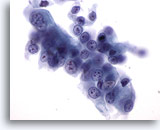

Figure 87

Bronchial wash

This cluster contains many abnormal cells. Their nuclear detail is seen at the periphery of the cluster. 20x

Bronchial wash

This cluster contains many abnormal cells. Their nuclear detail is seen at the periphery of the cluster. 20x

Figure 87

Bronchial wash

This cluster contains many abnormal cells. Their nuclear detail is seen at the periphery of the cluster.

20x

Bronchial wash

This cluster contains many abnormal cells. Their nuclear detail is seen at the periphery of the cluster.

20x